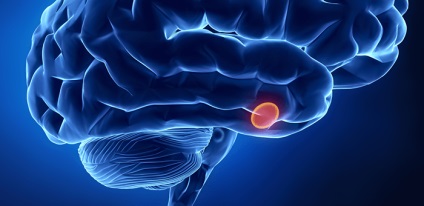

Beletelik egy hónap ... és így tovább, és a havi, és nem jön. A terhességi teszt is negatív. Világossá válik, hogy a Tanács nem tudja barátnője, valamit tenni kell, és a leginkább elfogadható ebben a helyzetben, forduljon orvosához. Miután interjút és szűrés az orvos válaszoljon a kérdésre, hogy miért a menstruációs ciklus megszakítása után OK nem kapunk. Mint általában, ez egy szindróma gipertormozheniya agyalapi mirigy működés és ennek következtében ez a szindróma másodlagos amenorrhoea.

- Az elülső nyúlvány lebeny (adenohipofízis).

Hogyan blokkolja az ovuláció? Blokkoló jelenség szintjén a hipotalamusz-hipofízis rendszer. Egyszerűen fogalmazva, a következő történik: be a szervezetbe kívülről hormon tabletták „jelentés” alapján a visszajelzések a hipotalamuszban, amelyek jelenleg a kereslet generáció felszabadító faktorok, a gonadotropin sem. Hipotalamusz-hipofízis rendszer reagál engedelmesen, és akadályozza a munkájukat a recepción fogamzásgátló tablettát.

Jellemzői az agyalapi mirigy

Van egy szempontból, hogy egyes nők genetikailag programozott veleszületett készségét az agyalapi a blokkoló hatás ösztrogén-progeszteron. Ez a verzió merült fel annak a ténynek köszönhető, hogy a felmérés szerint csökkent a mérete sella - az úgynevezett koponya, amely az agyalapi mirigy.

gonadotropin termékek ezek a lányok csökken, nincs benne rejlő közelgő ovuláció emelkedik hormon szintjét. A reakciót a méh és a petefészkek ebben az esetben a másodlagos.

Ez az elmélet azt mondja, hogy nem állítja vissza ovulációs ciklus kinevezését hipofizishormonok kívülről.

A kezelés megkezdése előtt ellenőrizze, hogy a helyes diagnózis. Ezért amellett, hogy feltérképezzük a beteg meddig megszűnt menstruáló szembesült ezzel a problémával, ha közel van, egyes nőgyógyászati problémák szükséges ellenőrző a széken. Jól van ultrahang (pajzsmirigy és a kismedencei szervek), X-sugarak a koponya, MRI, adományoz vér szintjének meghatározása a hormonok.

- Hipofízis adenoma.

Amikor nyúlvány agydaganat (adenoma) gyakran előfordul amenorrhoea-galaktorrea szindróma. Miután a eltörlése OK már megugrott prolaktin a vérben, csökkent gonadotropin és az esztrogén.

Nagyon fontos, hogy meghatározzák az oka amenorrhoea-galaktorrea tanulmányt CNS katekolamin. Ha van egy kimerülése neurotranszmitterek ingerület átvitel hipotalamusz sejtek, a zár releasing luteinizáló hormon (LH felelős laktáció funkció) megnöveli a prolaktin, és ennek következtében, galaktoree.